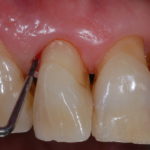

Deficit Vitamina C e sanguinamento gengivale

Lo studio conclude evidenziando che bassi quantitativi di vitamina C nel sangue coincidono con un’aumentata tendenza al sanguinamento in entrambi i gruppi di pazienti esaminati e questo fatto può essere visto come un punto importante e premonitore di una patologia micro vascolare che è reversibile con un aumento della dose giornaliera di acido ascorbico o vitamina C.

Sanguinamento gengivale come indicatore di patologia

Il sanguinamento gengivale può e deve quindi diventare un marker nella individuazione dei “bassi” livelli di acido ascorbico portando il dentista ad un controllo accurato dell’anamnesi alimentare del paziente e della sua assunzione di vitamina C che, ricordiamo, deve essere di almeno 85 mg./ die nella donna e 105 mg. /die nell’uomo, somministrata in piccolo dosi ripetute piuttosto che in un’unica dose massicciata (per approfondire leggete l’articolo Vitamina C e malattia parodontale)